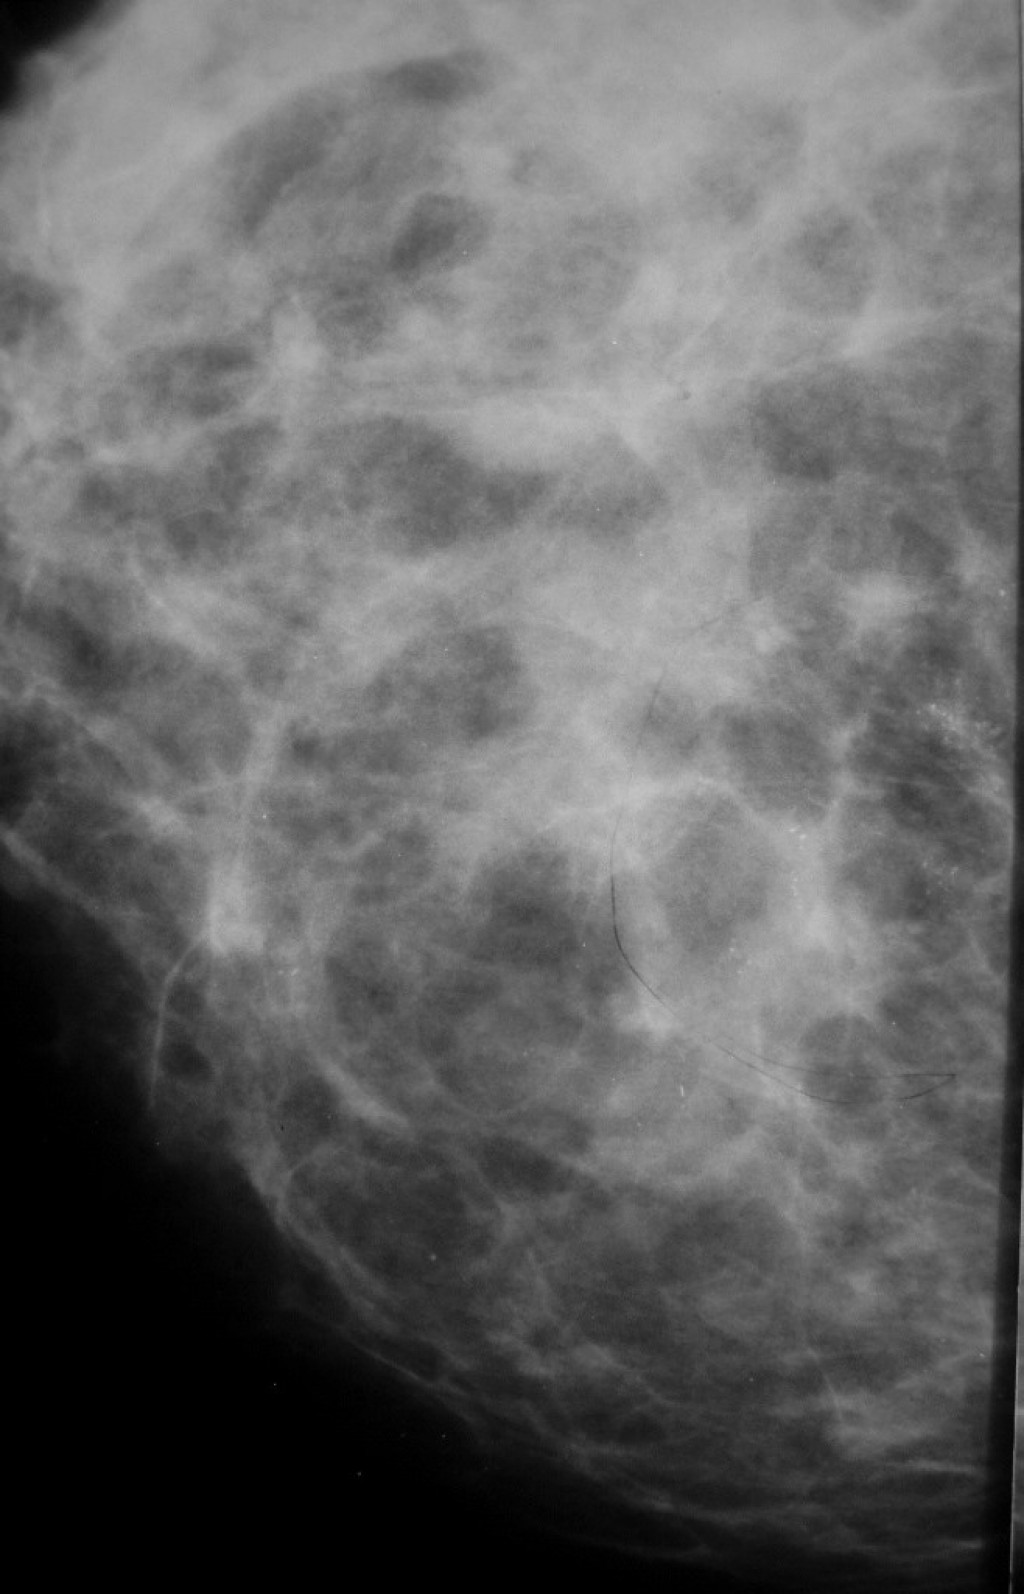

Фиброаденома молочной железы - доброкачественное образование, которое часто встречается у женщин. Оно может быть обнаружено при помощи различных методов диагностики, включая маммографию. Ниже представлены фотографии, помогающие понять, как выглядит данное заболевание.

Маммограмма кальцинаты визуализируются

Маммография и ее роль в диагностике фиброаденомы молочной железы

Маммография - это рентгенологическое исследование молочных желез. Оно позволяет выявить различные изменения в тканях, включая фиброаденому. На маммограммах можно увидеть структурные особенности опухоли и отследить ее динамику во времени.